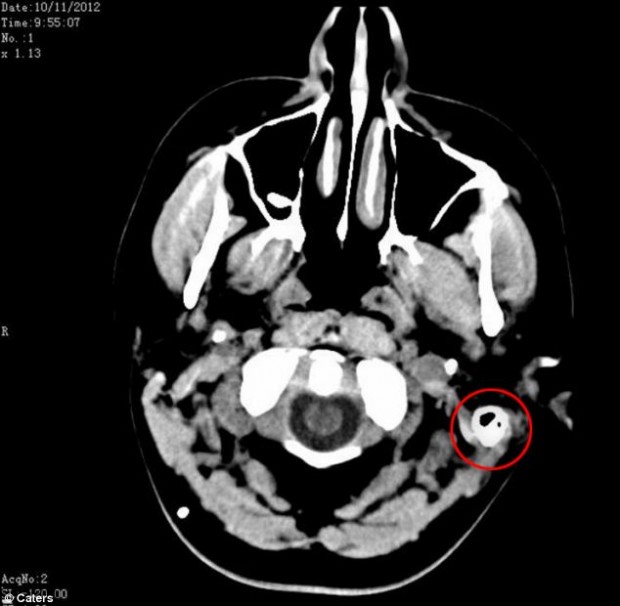

Сэм была направлена к целому ряду специалистов, которые подозревали, что у нее может быть опухоль мозга. К счастью, после проведения ряда тестов, опухоль головного мозга была исключена из списка возможных причин недуга. Тем не менее, врачи так и не смогли определить, что с ней случилось. Специалисты выяснили истинную причину ее проблем со здоровьем только после проведения люмбальной пункции.Человеческий мозг окружен жидкостью, которая предохраняет мозг от ударов о стенку черепа, но организм Сэм, как оказалось, производит этой жидкости в три раза больше нормы. Даже после постановки диагноза и принятия 17 различных препаратов в день, Сэм продолжала страдать от ужасных головных болей.

И только в мае прошлого года девушке был установлен шунт для слива лишней жидкости. Сэм надеялась на немедленное облегчение, но ее мозгу потребовалось время, чтобы привыкнуть к инородному телу. Спустя некоторое время Сэм приспособилась к изменениям и с тех пор она снова живет нормальной жизнью.